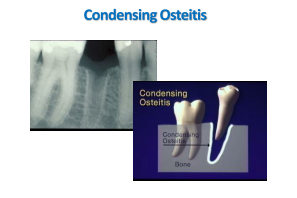

Third molars out – leaves cavitations

they’re lined with lots of toxic rations

Oozing out a toxin blend

which immune systems cannot defend

Left unattended, a sick tooth will grow

a calcium lining which doesn’t show

This is condensing osteitis

the pain from which really ignites us

Fibromyalgia the pain is called

from the contaminated calcium wall

X-rays and psychiatrists cannot find

what’s driving us out of our mind